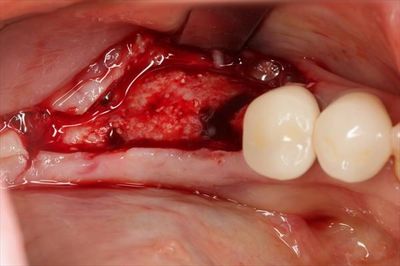

粘膜を剥離して骨の状態を確認し、ドリリングを進めます。

インプラントはスイスのストローマンインプラントです。

BLT φ4.8 10㎜ Roxolid (TiZr:チタンジルコニウム) SLActive